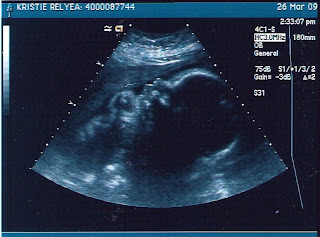

Baby B is One BIG Boy!

Today we got a peek at Baby B's never-ending activity....and Mommy nearly croaked when she found out just how big of a boy he is! Weighing in at 4 pounds 11 ounces - he's close or above the 90th percentile with all measurements (yikes!).

The sono tech and Dr. Bartol commented on what a busy boy he is. He's nice and comfy in a head-down position with his feet cramped under Mommy's left rib. Daddy thinks he's going to look like Mommy from the glimpses of his eyes and their shape. Mommy is still in shock over the minor size concern, since he's expected to gain 1/2+ pounds a week from here on out. Yeah, 8 more weeks to go and already close to 5 pounds - maybe we'll need to have a newborn "bringing baby home" outfit and an option in a 3-month size!